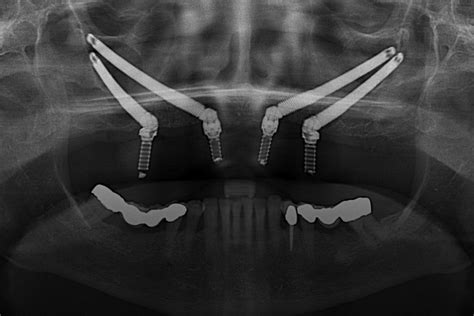

Los implantes cigomáticos son implantes largos que se colocan en el hueso malar en personas sin hueso suficiente para implantes dentales normales. La mayoría de las veces pueden efectuarse rehabilitaciones fijas en un día y generalmente, con anestesia local y sedación.

El equipo del Dr. Álvarez Gimeno posee una de las mayores experiencias de éxito en España y son instructores de la técnica para otros dentistas y cirujanos maxilofaciales.

Implantes cigomáticos para pacientes con poco hueso maxilar superior